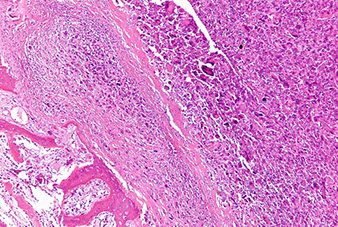

Anaplastic, high-grade malignant small round blue cell tumor MC in boys <15 yo

- may present as warmth and swelling in the diaphysis of long bones and in pelvis, scapula and ribs (bone involvement assoc c soft-tissue extension, can occur in any bone)

- another micro feature is Homer-Wright pseudorosettes and spotty necrosis

Micro: uniform small round blue cells, eosinophilic cytoplasm

- monotonous nuclei ,inconspicious nuclei and low mits are deceptively low grade

- occasionally has Rosettes

Ewing's sarcoma / PNET

A, Ewing sarcoma consists of solid sheets of small, blue, round cells with geographic necrosis and nuclear expression of Friend leukemia integration 1 transcription factor (FLI1) (B).